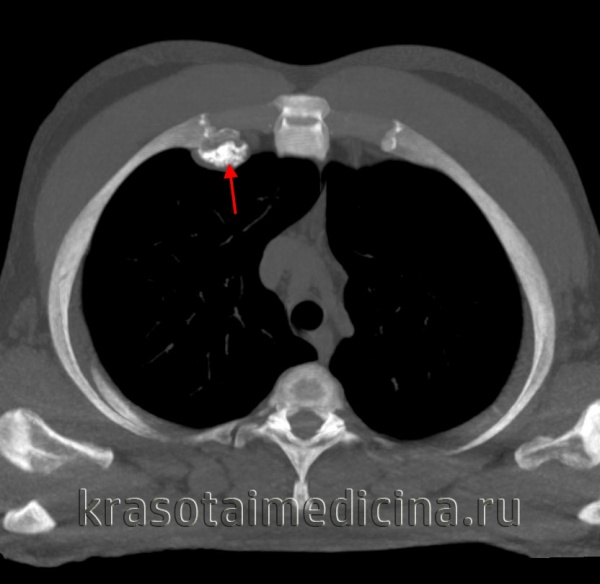

Крупная остеохондрома проксимальной части малоберцовой кости: рентгенограмма (а), трехмерная КТ-реконструкция (б), КТ-срез (в). Образования этой локализации могут стать причиной нейропатии малоберцового нерва.

В данном случае имеется выраженная вогнутая деформация прилежащего кортикального слоя большеберцовой кости, являющаяся примером вторичной деформации кости вследствие экспансивного роста остеохондромы. Остеохондрома на ножке дистального отдела бедра. Образования обычно растут в противоположную от суставов сторону. Спонгиозная часть остеохондромы сообщается с костно-мозговым каналом пораженной кости. Образование сохраняет единство кортикального и спонгиозного слоя с материнской костью, что является рентгенологическим признаком остеохондромы. Остеохондрома на широком основании дистального конца большеберцовой кости. Обратите внимание на угловую деформацию пилона большеберцовой кости. Образования подобной локализации могут приводить к нарушению роста и угловой деформации костей. Множественный остеохондроматоз, сопровождающийся деформацией костей. Это наследственное заболевание с аутосомно-доминантным типом наследования. Пациент с симптоматикой, обусловленной компрессией большеберцового нерва. Рентгенограмма коленного сустава пациента с множественными остеохондромами. Имеются множественные поражения дистального отдела бедра и проксимального отдела большеберцовой кости и сопутствующая деформация конечности. Интраоперационная картина остеохондромы. Обратите внимание на непрерывность кортикального слоя и «шапку», образованную зрелой хрящевой тканью. Микропрепарат остеохондромы. Гистологически эти образования выглядят также, как зоны роста костей — хрящевая ткань, созревающая путем энхондрального окостенения и превращающаяся в нормальную костную ткань. Макропрепарат остеохондромы. Обратите внимание на хрящевую «шапку» с сохранением непрерывности костно-мозгового пространства остеохондромы и пораженной кости.